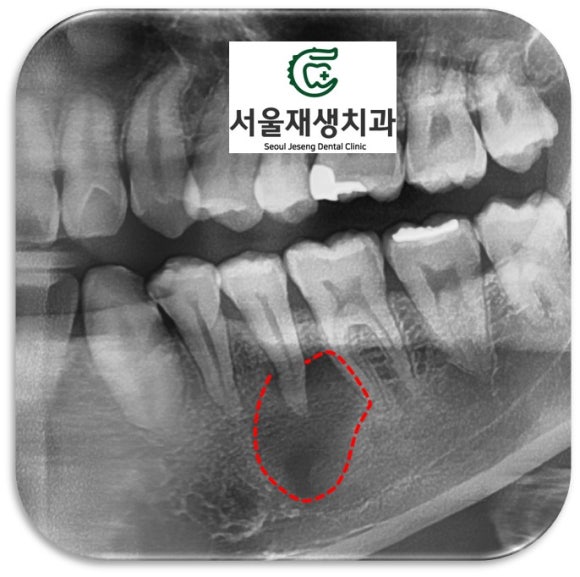

X-ray를 통해 뿌리 끝 염증을 관찰!

치과 엑스레이 검사의 가장 기본이 되는

파노라마 엑스레이입니다.

조금만 더 확대해볼까요?

아하...

아래 어금니 앞에 있는

작은 어금니의 뿌리 주위로

심상치 않은 기운이 느껴집니다.

뼈를 광범위하게 녹이고 있는

뿌리 끝 염증!!

치아 신경은 이미 감염되었고,

감염 부산물들이 뿌리 끝에 나있는

작은 구멍을 통해 배출되다보니

뼈까지 손상을 시키게 된 것이죠...